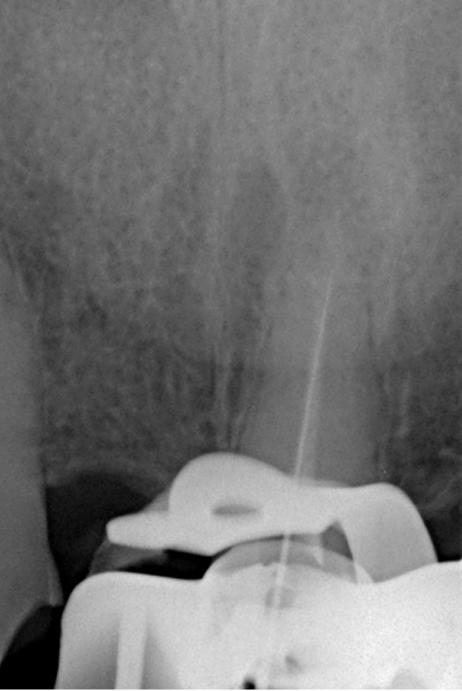

Выявлена болезненность при перкуссии и пальпации в области 21 зуба. Зуб не реагирует на термические раздражители. Результаты пародонтологического обследования в пределах нормы, рентгенологическое обследование выявило радиолюцентную зону в области верхушки корня (снимки 1, 2).

Диагноз: Острый апикальный периодонтит.